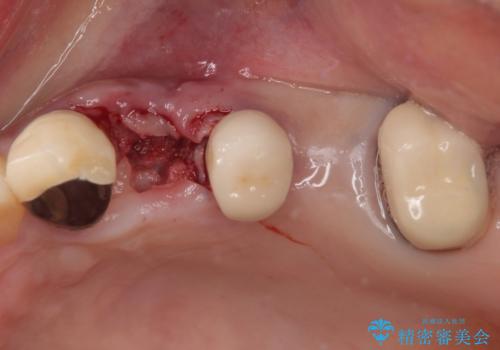

- 抜歯が必要と言われ、インプラント治療を希望して来院された患者様です。

歯がボロボロで抜歯が必要な状態であり、後方にはインプラントが埋入されているため、同様にインプラントによる補綴治療を行うこととしました。

クラウンを装着できないため、プラスチックを歯に流し込んで仮歯のようにしている状態でした。

プラスチックを外すと同時に抜歯を行い、1ヶ月ほど待機して歯肉が落ち着いたことを確認してから速やかにインプラントを埋入することとしました。

従来は4ヶ月ほど待機してからの埋入が一般的でしたが、歯肉の炎症が落ち着いた時点で速やかに埋入できるようになり、4ヶ月の短期間で治療を終えることができました。